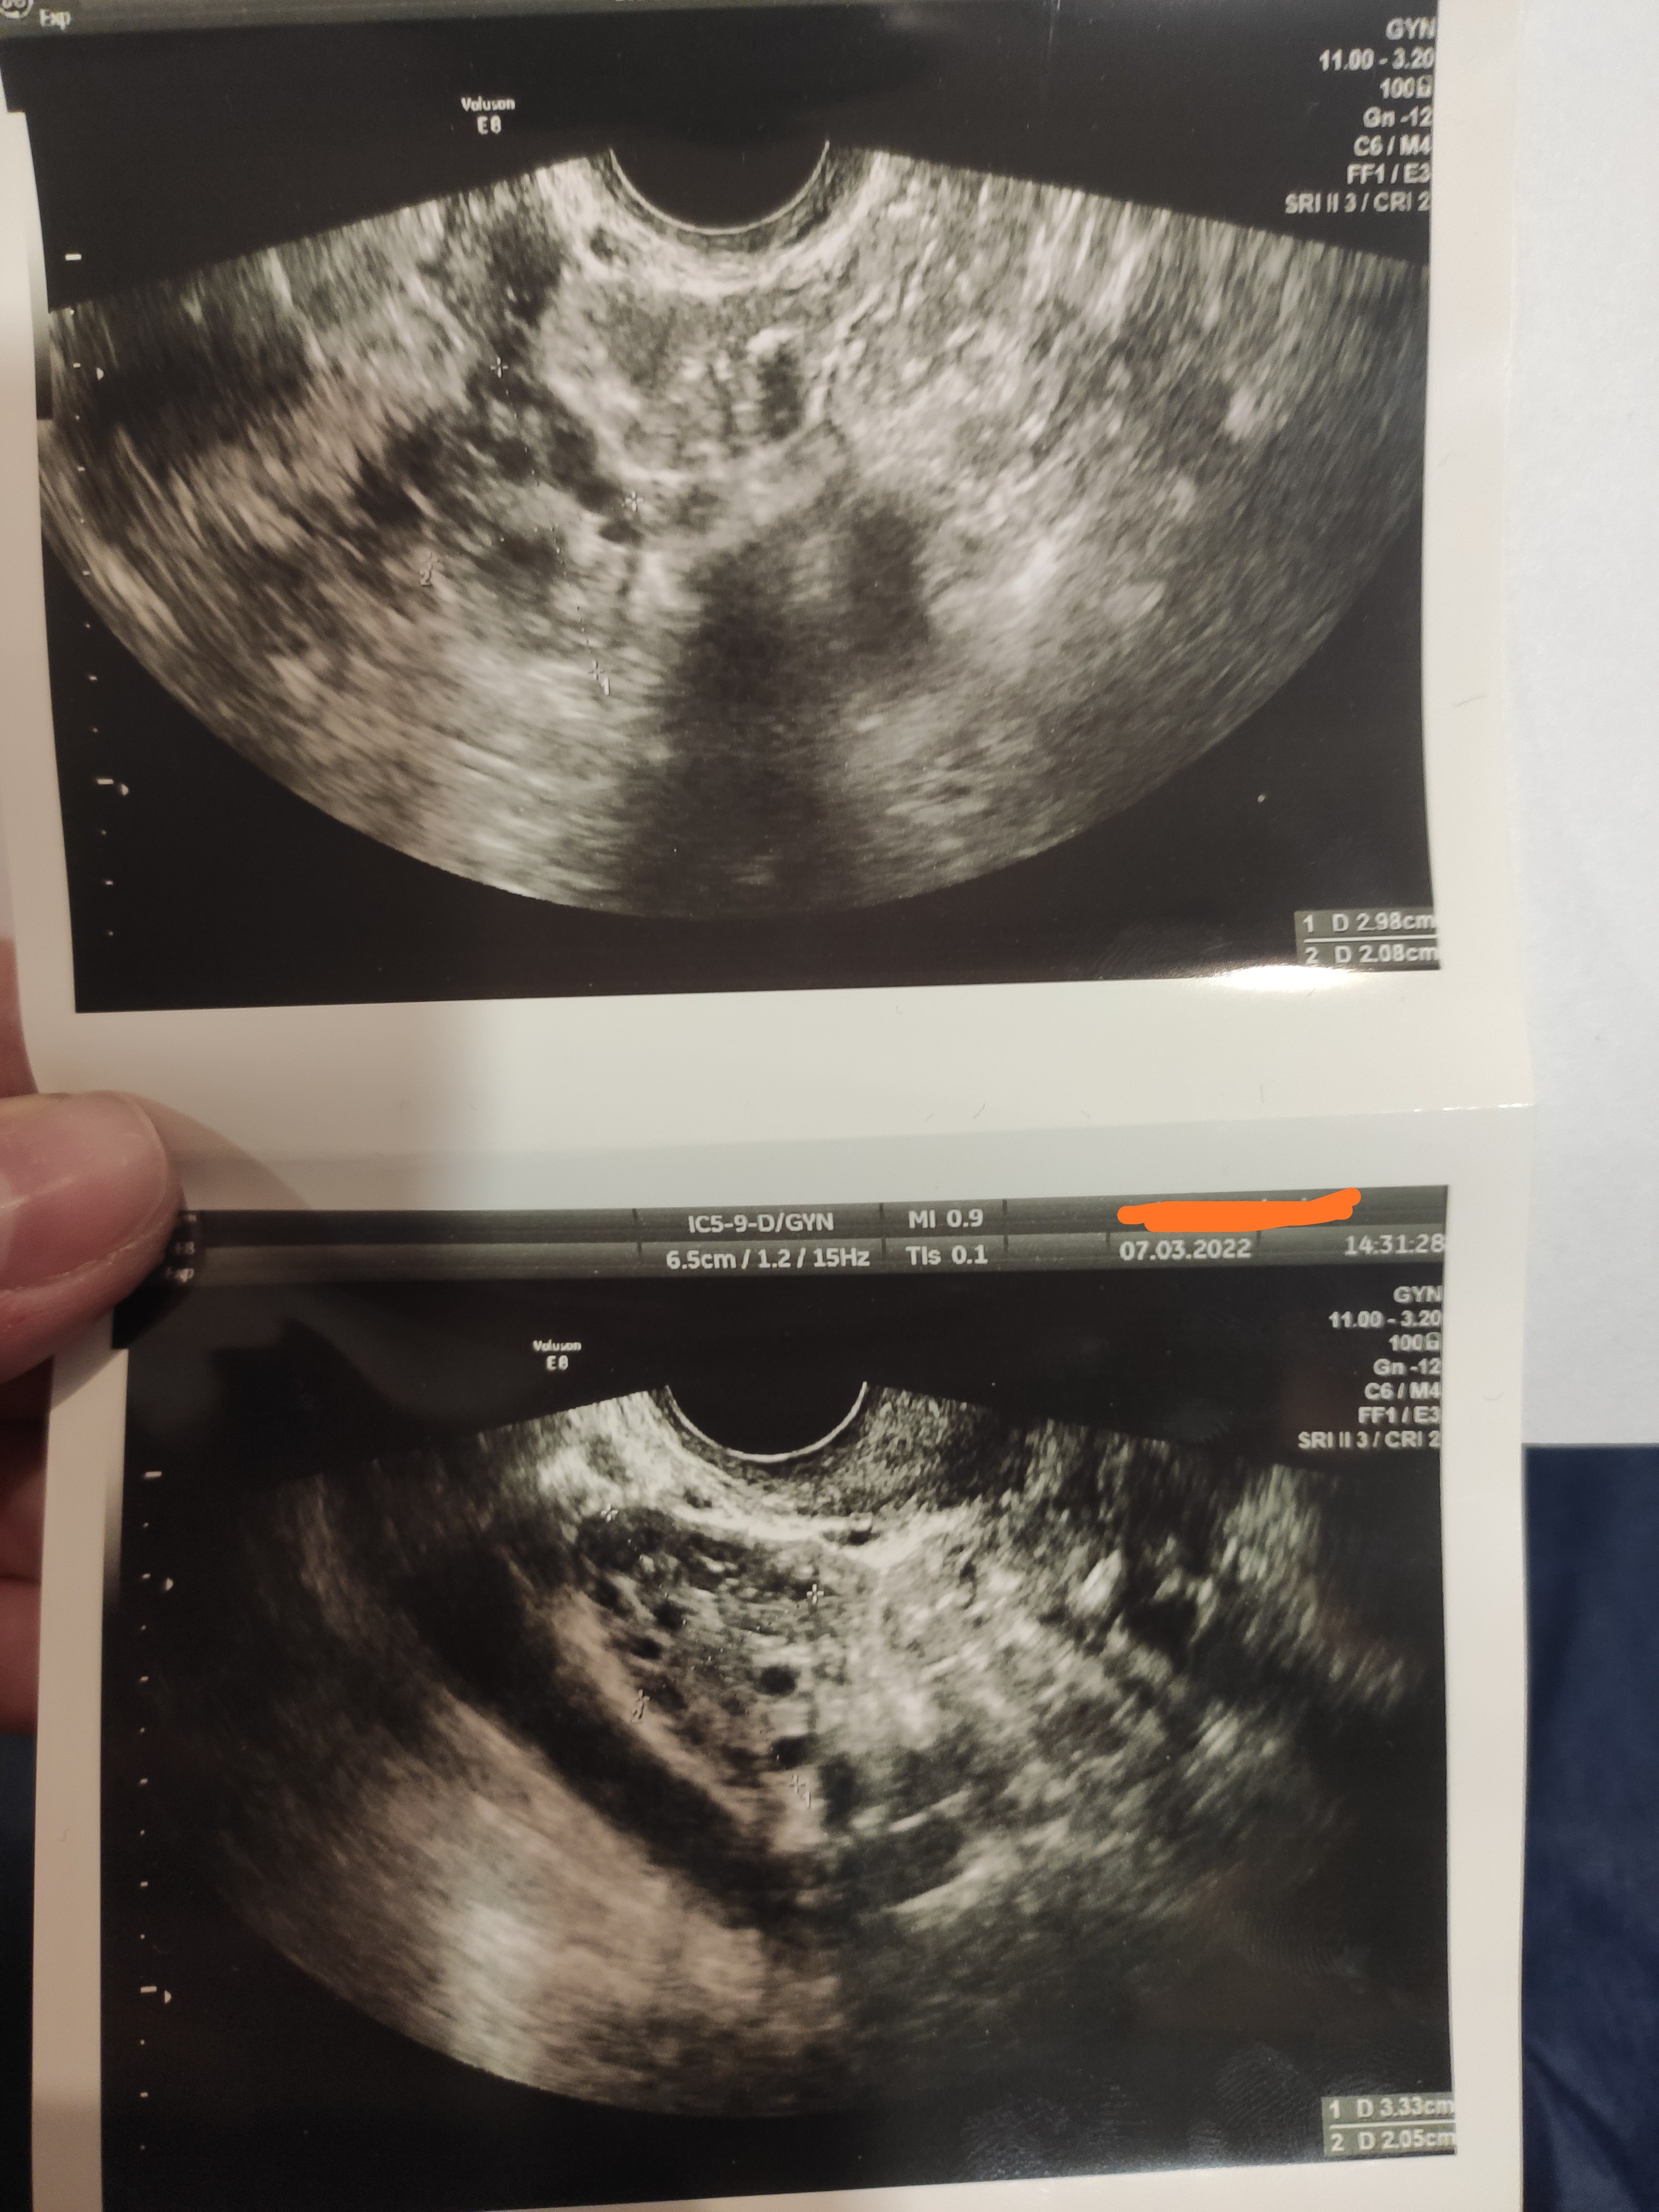

miałam dzisiaj wizytę u gina i mam mieszane uczucia... Jestem w 16dc, cykle mam ok 28 dni, faza lutealna 11 dni więc owulacje wypadają między 16-18 dc, może raz w ciągu roku zdarzylo się w 15dc. No i zadowolona dzisiaj że może dowiem się kiedy będzie owu, czy dzisiaj czy w ciągu dwóch dni dowiedziałam się, że albo owu była wczoraj albo nie będzie jej wcale

nie ma żadnego pęcherzyka dominującego, jest trochę płynu w zatoce Douglasa i coś co może być ciałkiem żółtym ale w sumie to nie wiadomo... Endo grube bo prawie 14 mm, ale po wykresie temp w ogóle nie widać żeby rzeczywiście ta owu wczoraj była

załączam zdjęcia USG , opis i wykres temp może jakaś dobra dusza zerknie czy widzi coś co mogłoby sugerować że ta owu była czy nie